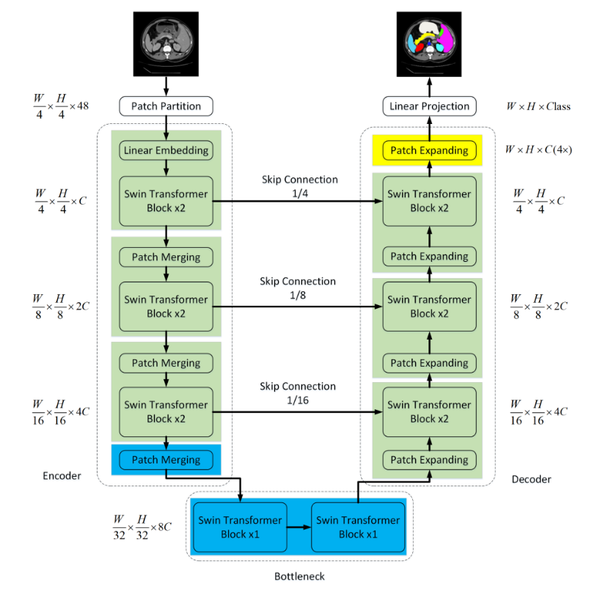

Within the domain of medical image segmentation, the demands for precision are exceedingly high. While CNN segmentation algorithms have achieved significant advancements in recent years, they still fall short of the stringent criteria required for medical applications. To address this gap, the Swin-Unet network was introduced, merging the capabilities of U-Net with the Swin Transformer. Figure 2 illustrates the comprehensive structure of this network.

Encoder Part: The Swin-Unet network significantly modifies the convolutional pooling operations of the original U-Net network, replacing them with multiple basic unit blocks from the Swin Transformer network. Each unit block in the network is capable of computing self-attention through local and global perception layers, allowing it to capture image features at various scales.

Decoder Component: Comparable to the U-Net architecture, Swin-Unet incorporates skip connections during upsampling, reinstating the reduced feature maps to the original image dimensions. However, the key distinction lies in replacing conventional convolutional operations with Swin Transformer blocks for feature learning.

|

| Figure 2. Swin-UNet network architecture diagram |